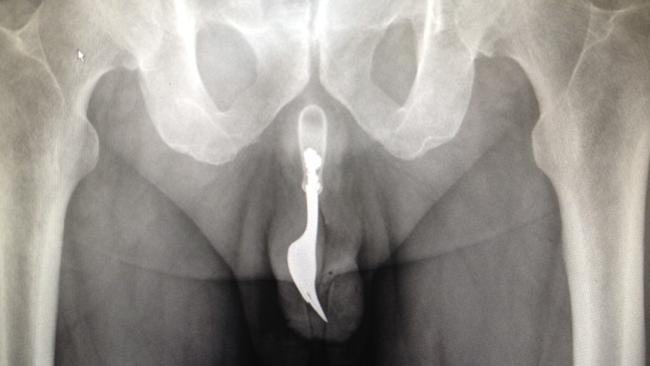

据英国《都市日报》报道,近日,马其顿共和国22岁的男子奥利弗·艾力克(Oliver Ilic)因被女友嫌床技不好而甩后,竟在伤心之余,一怒之下用剃须刀刀片将自己不争气的阴茎切了下来,并丢到垃圾桶里。 据悉,奥利

据悉,奥利弗对医生诉苦,觉得自己的小阴茎就是他被女友甩的罪魁祸首。在他看来,这样没用的东西不如切掉。冲动之下,奥利弗就自己动手用剃须刀刀片将阴茎切除。

不料,切口一直流血不止。最终,奥利弗不得不拨打医院的急救电话求救。

随后,警方搜查奥利弗的房屋时,在垃圾桶内发现被他切断了的器官,遂将这个血肉模糊的器官送往医院。最终,被转往首都医院的奥利弗,在接受了一场长达5个小时的缝合手术后,终于挽回了他的重要器官,并确保性命无虞。 目前,医方还不能确定奥利弗的手术是否成功,这取决于他受伤部位的功能是否恢复如初。